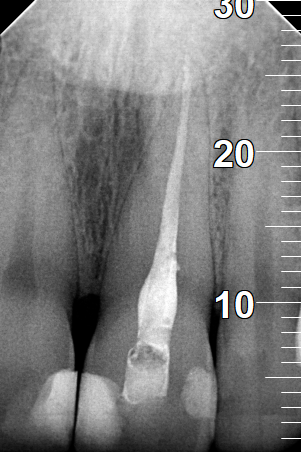

Pus after opening the tooth

Clinical photo of root canal filling

Final photo of the tooth after the root canal treatment